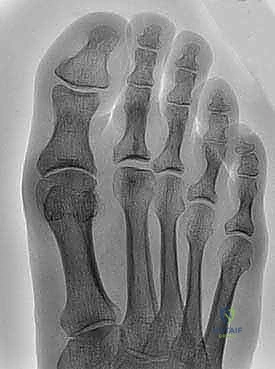

Standard posteroanterior (PA) and lateral radiographs of the wrist are obtained. The lateral radiograph must be a true, zero-rotation lateral, defined strictly by the collinearity of the palmar cortices of the pisiform and the scaphoid pole, to accurately assess dorsal or volar subluxation of the ulnar head relative to the radius. Grip-loaded PA views can demonstrate dynamic ulnar positive variance, highlighting incompetence of the longitudinal stabilizers.

Advanced imaging, specifically computed tomography (CT), is the gold standard for evaluating the cross-sectional morphology of the sigmoid notch, the version of the joint, and the absolute degree of radioulnar subluxation. Axial cuts obtained in neutral, full pronation, and full supination can definitively map the kinematics of the joint, identify the primary zone of impingement, and quantify arthritic change.